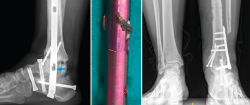

Figura 5. Imágenes de tomografía computarizada con el clavo roto. Finalización de la extracción con la guía curvada a través de la luz del clavo. Rescate con placa tibiotalocalcánea e injerto corticoesponjoso colocado en el foco.

Se reintervino al paciente realizando la extracción del fragmento distal del clavo sin dificultad. Para la extracción del fragmento proximal, se practicó, como en el caso anterior, además de la utilización de las guías curvadas, en el foco de pseudoartrosis, una muesca en el clavo con la fresa de alta velocidad para apoyar el escoplo. De ese modo, con la ayuda de la percusión directa sobre el clavo, se consiguió la extracción del extremo proximal a través de la planta del pie. Tras legrar las superficies articulares y aportar injerto tricortical de cresta ilíaca, se realizó la fijación con una placa de artrodesis TTC (Palex Medical) (Figura 5).